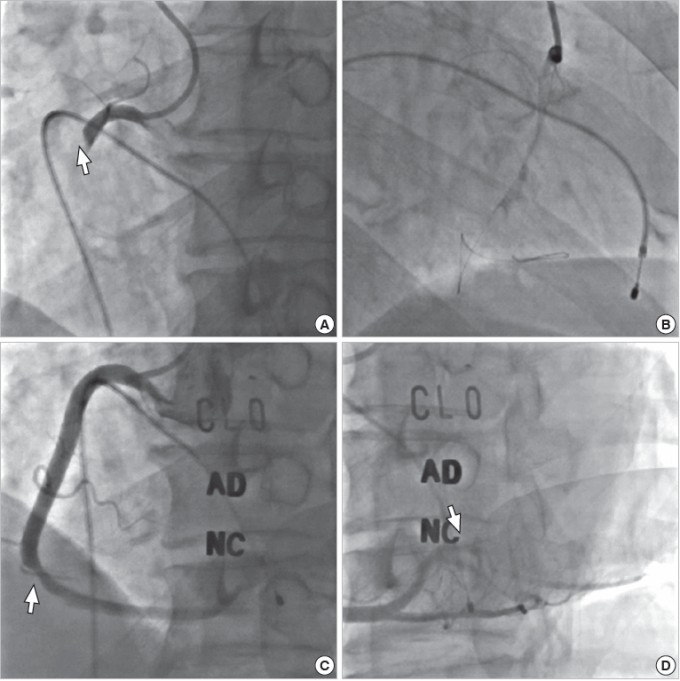

Các bác sĩ khoa cấp cứu, hồi sức tích cực và đơn vị tim mạch can thiệp nhận định, bệnh nhân bị nhồi máu cơ tim cấp có biến chứng sốc tim, rối loạn nhịp rất nặng, đã thống nhất xử lý thuốc cấp cứu, cho thở máy và chuyển ngay tới phòng can thiệp tiến hành đặt máy tạo nhịp tạm thời vào buồng thất phải, giúp bệnh nhân duy trì huyết áp và nhịp tim. Đồng thời chụp mạch vành qua da cấp cứu.

Qua hình ảnh chụp động mạch vành, bệnh nhân bị tắc hoàn toàn động mạch vành phải, do cục máu đông ở vị trí gần ngay lỗ vào (điểm xuất phát của động mạch vành phải). Kíp kỹ thuật đã can thiệp tiến hành nong và đặt stent thành công, tái lập dòng chảy động mạch vành. Sau khi can thiệp, bệnh nhân được chuyển về khoa hồi sức tích cực tiếp tục điều trị nội khoa. Đến nay, đã tỉnh táo hoàn toàn, sức khỏe ổn định, nhịp tim hồi phục trở lại, không cần sự trợ giúp của máy tạo nhịp nữa.